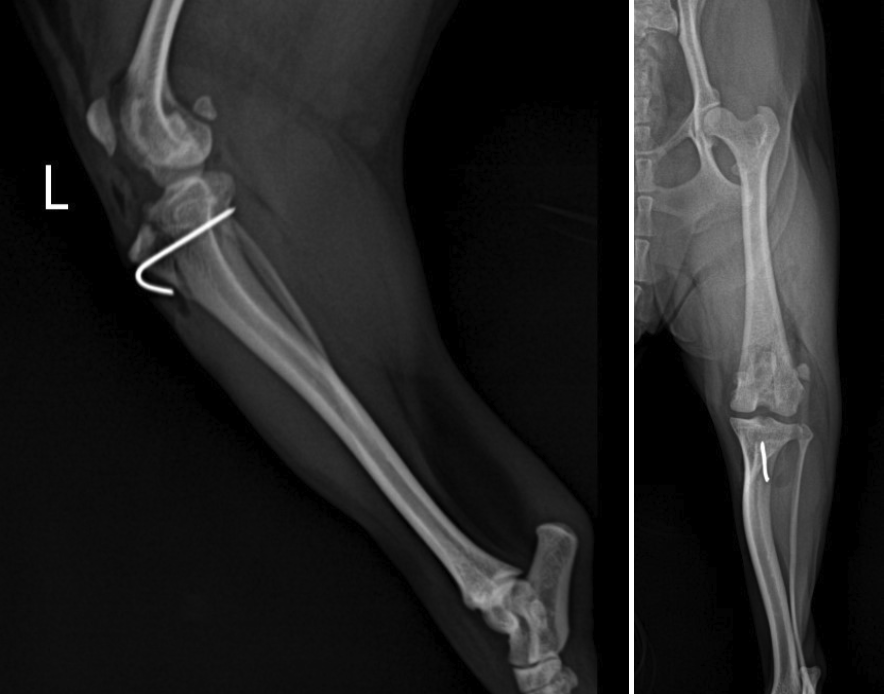

수술 후에는 후지 엑스레이 촬영을 통해 슬개골의 위치와 무릎 관절 정렬 상태를 다시 확인했습니다.

수술 후 방사선 사진 / 출처: 미래동물의료센터

수술 전 내측으로 벗어나 있던 슬개골이 대퇴골 고랑 안에 안정적으로 위치해 있었으며, 정강이뼈 정렬 역시 의도한 방향으로 교정된 것을 확인할 수 있었습니다. 현재는 입원 치료를 마친 뒤 퇴원하여 통원 관리와 함께 재활 및 회복 과정을 이어가고 있으며, 보행 상태와 관절 안정성을 지속적으로 관찰하며 단계적인 회복 관리가 진행 중입니다.